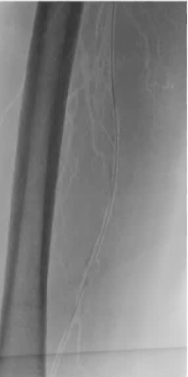

经皮血管内裸支架植入术

为了改善血管内治疗的效果,包括狭窄性病变,夹层病变,以及预防再狭窄,支架的材料,结构和药物涂层技术不断发展, 但也有人认为只要考虑其结构(scaffolding)就足够 为什么裸金属治疗,主要用于 1. 机械性的治疗血管狭窄、夹层 2. 预防再狭窄,减少新生内

1. “机械性”的治疗血管狭窄、夹层

2. 预防再狭窄,减少新生内膜增生(neointimal proliferation)